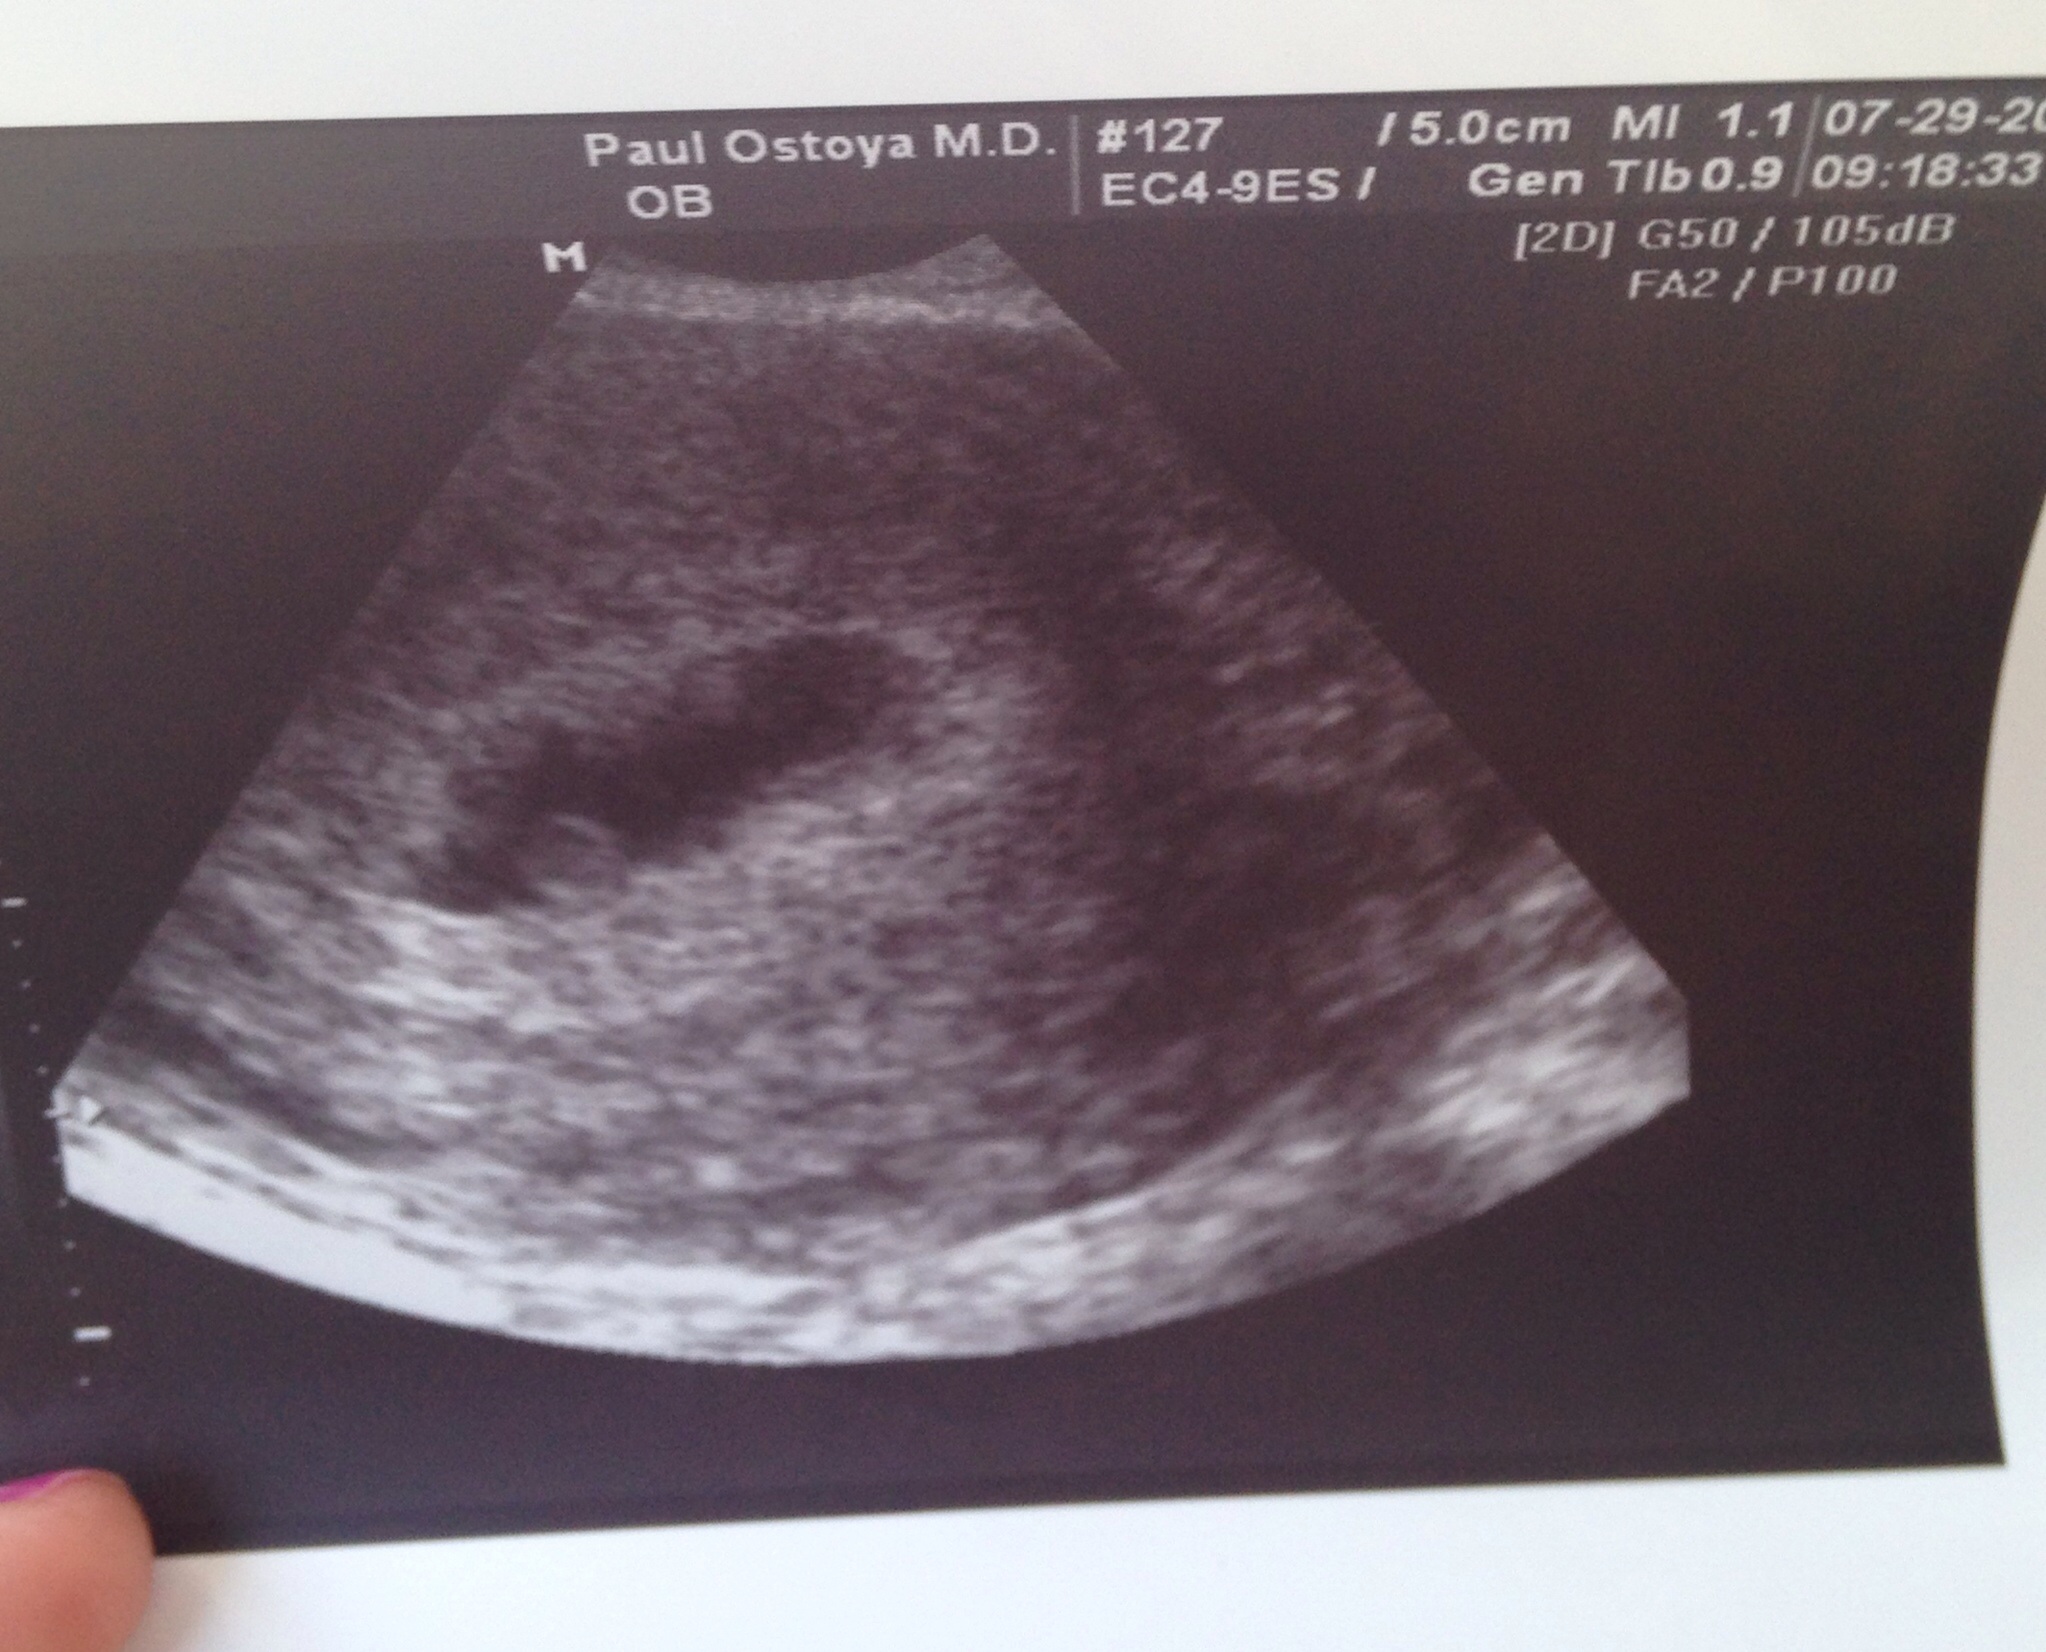

This was taken transvaginally at 6w1d.

And here is my sons from 6w6d taken on the same u/s machine